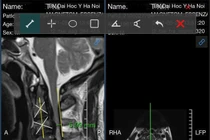

(khoahocdoisong.vn) - Mất đường cong sinh lý cổ gây tăng áp lực lên các đĩa đệm đốt sống cổ không chỉ gây thoái hóa hoặc thoát vị đĩa đệm mà còn giảm máu lưu thông lên não gây nhiều bệnh lý khó lường.